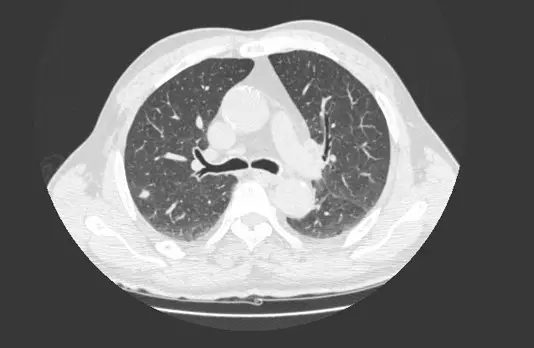

下圖是由那一種影像設備拍攝?

A胸部電腦斷層掃描(chest CT)

B胸部 X 光(chest X-ray radiography )

C胸部超音波(chest ultrasound)

D胸部正子造影(chest PET)

- 切面方向(Plane):影像呈現的是標準的軸切面(Axial view / Transverse plane),也就是將人體橫切的視角。影像上方為前胸(Anterior),下方為後背(Posterior),左側為人體的右邊,右側為人體的左邊。

- 組織密度與對比(Tissue Density & Contrast):

- 肺野(Lungs):呈現大片深黑色,代表充滿空氣(極低密度)。同時可清晰看見白色的肺血管與氣管分支網絡分布其中。

- 骨骼(Bones):影像最下方的脊椎(Spine)、周圍的肋骨(Ribs)以及最上方的胸骨(Sternum)均呈現極亮的白色,代表高密度(高 X 光衰減)。

- 縱膈腔(Mediastinum):位於中央的軟組織(心臟大血管結構)呈現均勻的淺灰色。

- 氣道(Airway):中央可見氣管分叉處(Carina level),左右